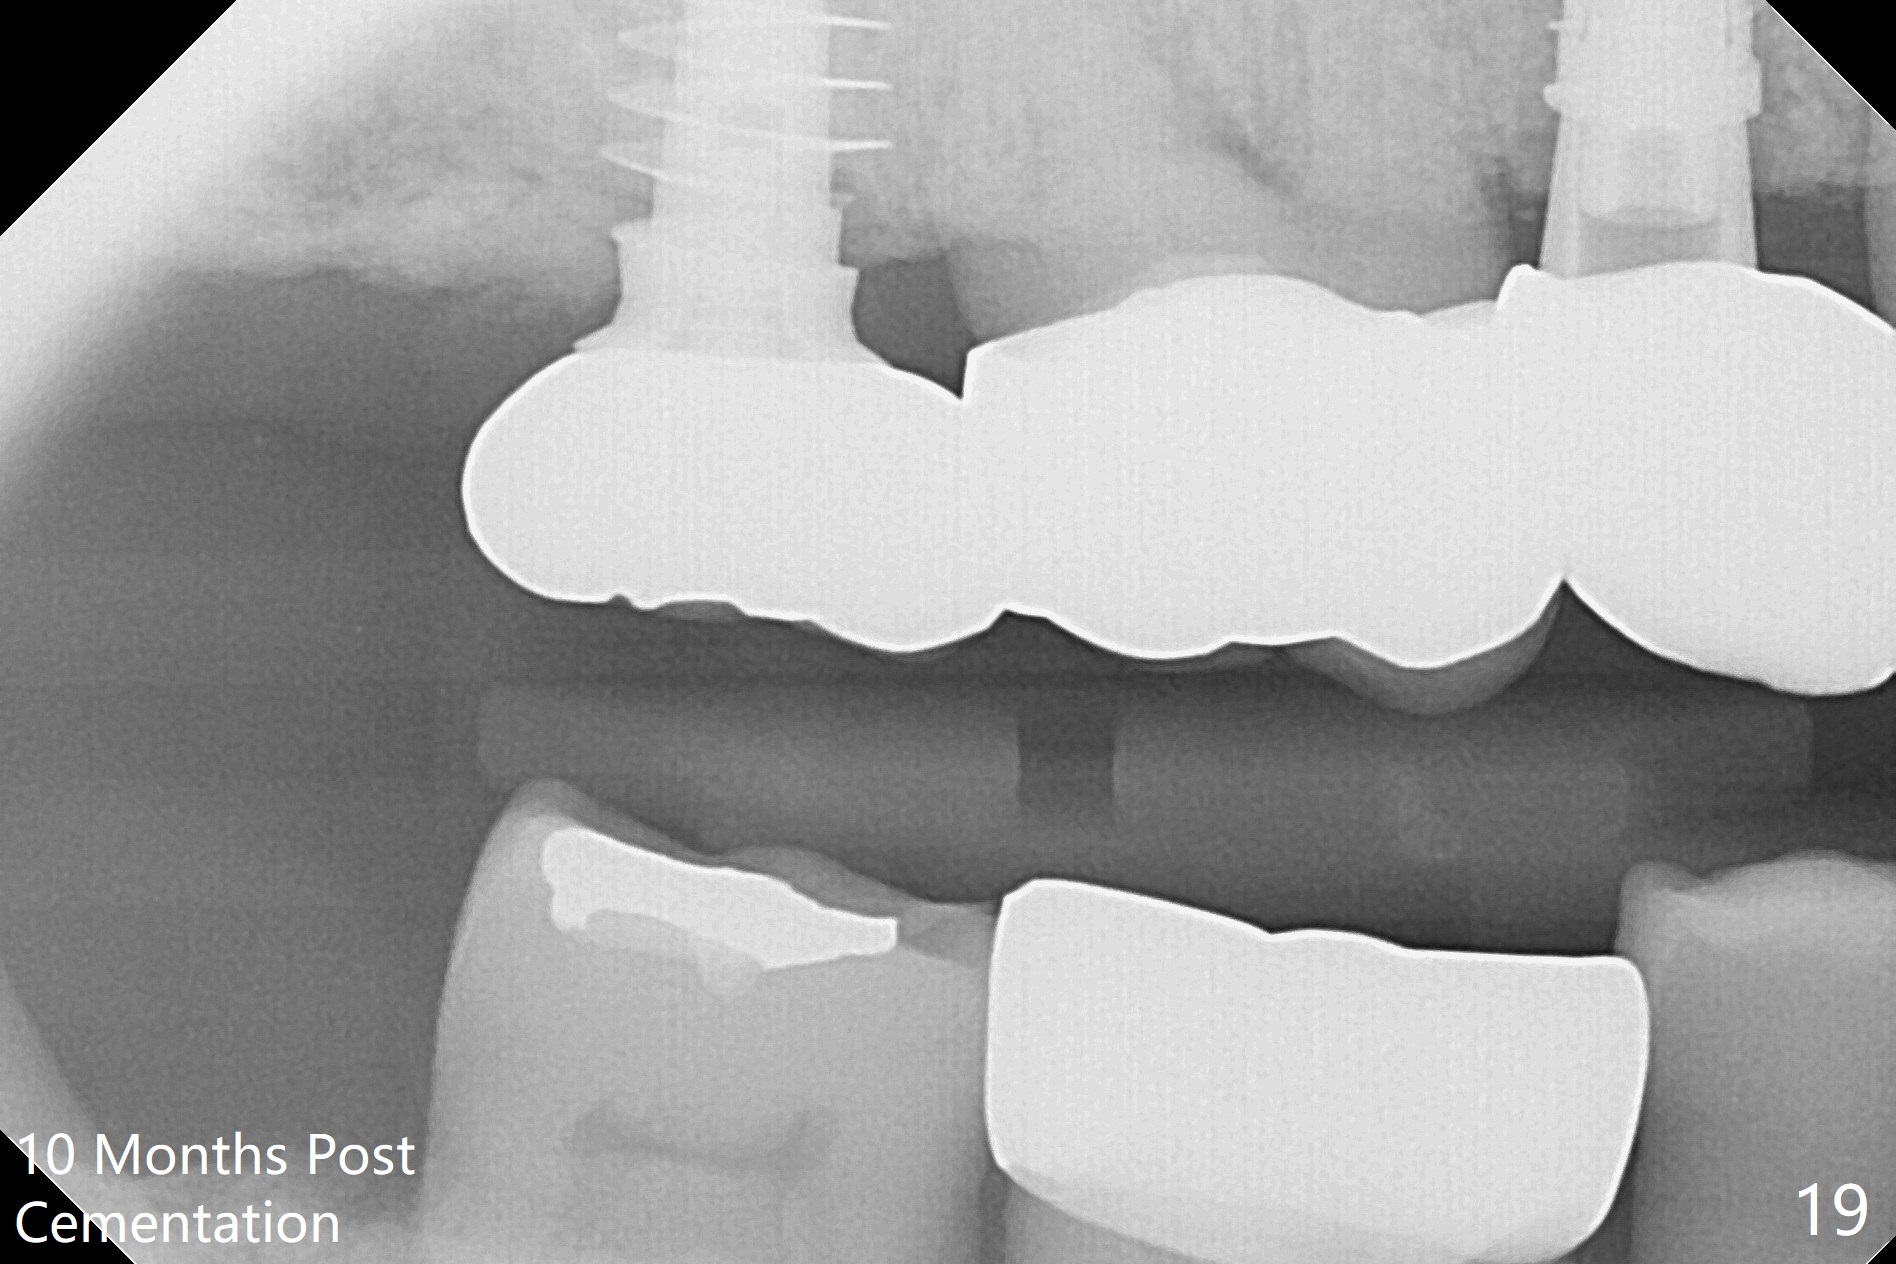

The right posterior final restorations (Fig.14) are fabricated as planned: increase in vertical height (Fig.15). The increase is minimal (Fig.14, 17(#2 limited crown height), 16 (#2 crown being thin *)). Fig.17,18 are taken immediately post cementation. There is no bone loss 10 months post cementation (Fig.19,20). The gingiva is healthy around the implant crowns (#2, 4 and 28) 1 year 4 months post cementation (Fig.21,22).